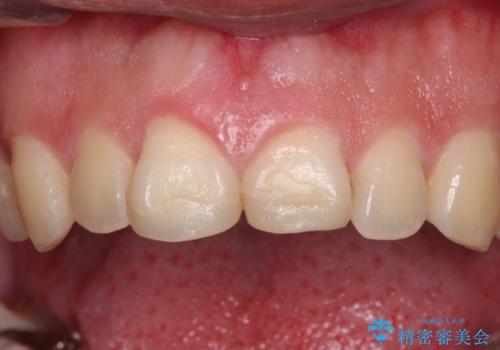

- 競技用自転車を運転中に転倒して前歯を強くぶつけ、欠けてしまったとのことで来院された患者様です。

近医にて欠けて部分を樹脂で修復してもらったものの、舌での感触が悪く、しみる感覚があるため、オールセラミッククラウンによる補綴治療を希望されていました。